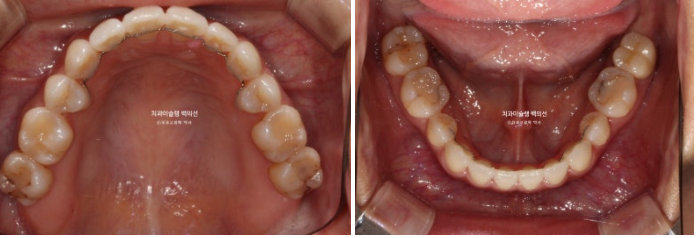

25년 2월 교정치료를 위해 온 환자분입니다.

오래 전 발치교정을 했는데 유지관리 단계에서 다시 틀어져 버렸습니다.

그 당시 원장님이 철사유지장치는 안해주고 뺏다꼈다 하는 유지장치만 줬다고 합니다.

이렇게 철사 고정식 유지장치를 붙여놓지 않고 뺏다 꼈다 하는 유지장치로만 좋은 결과를 유지하는 것은 한계가 있습니다.

요즘은 철사 고정식 유지장치는 필수입니다.

아랫니도 약간의 배열 불규칙이 보입니다.

인비절라인 익스프레스 권유드렸고 상악은 배열 위주, 하악은 치간삭제를 통해 블랙트라이앵글 사이즈를 줄이고 배열을 잡기로 합니다.